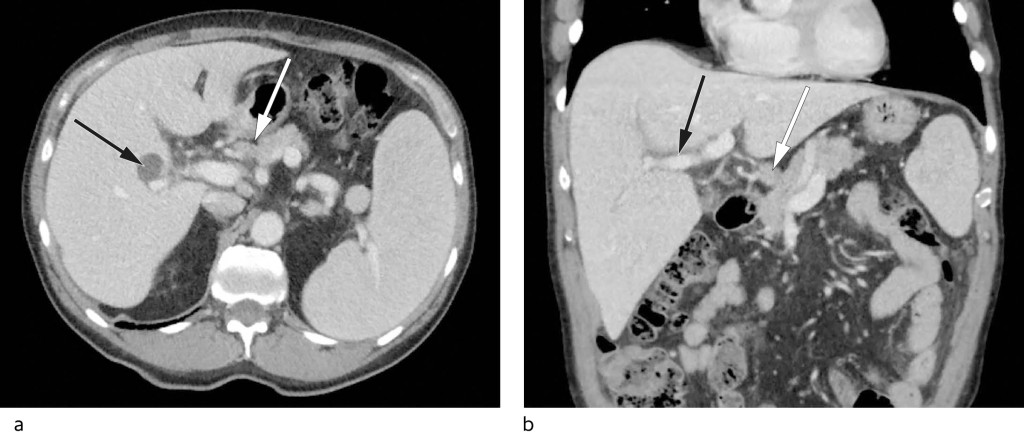

On account of his high sedimentation rate, anaemia, weight loss and altered general condition, the patient was referred for CT of the neck, thorax, abdomen and pelvis with intravenous contrast. This revealed small amounts of free fluid in the pelvis, splenomegaly of 17 cm (longest diameter), periportal oedema and prominent hepatic hilar lymph nodes, the largest with a short-axis diameter of 11 mm (Figure 1).

Figure 1 a) Axial CT of the upper abdomen with enlarged spleen and accessory spleen, prominent hepatic hilar lymph glands (white arrow) and a simple liver cyst in the right lobe (black arrow). b) Coronal CT with periportal oedema (black arrow) and prominent hepatic hilar lymph gland (white arrow).

Periportal oedema, the accumulation of fluid in tissues surrounding the portal venous system, is a nonspecific finding that may indicate liver pathology, but that can also be seen in extrahepatic diseases (5). A number of disorders can give rise to splenomegaly, including portal hypertension secondary to liver disease, as well as lymphoma and other haematological malignancies. However, lymphoma was less likely given the isolated finding of slightly prominent hepatic hilar lymph nodes in the absence of enlarged lymph nodes elsewhere. The anaemia, M-component, and left shift suggested haematological disease.